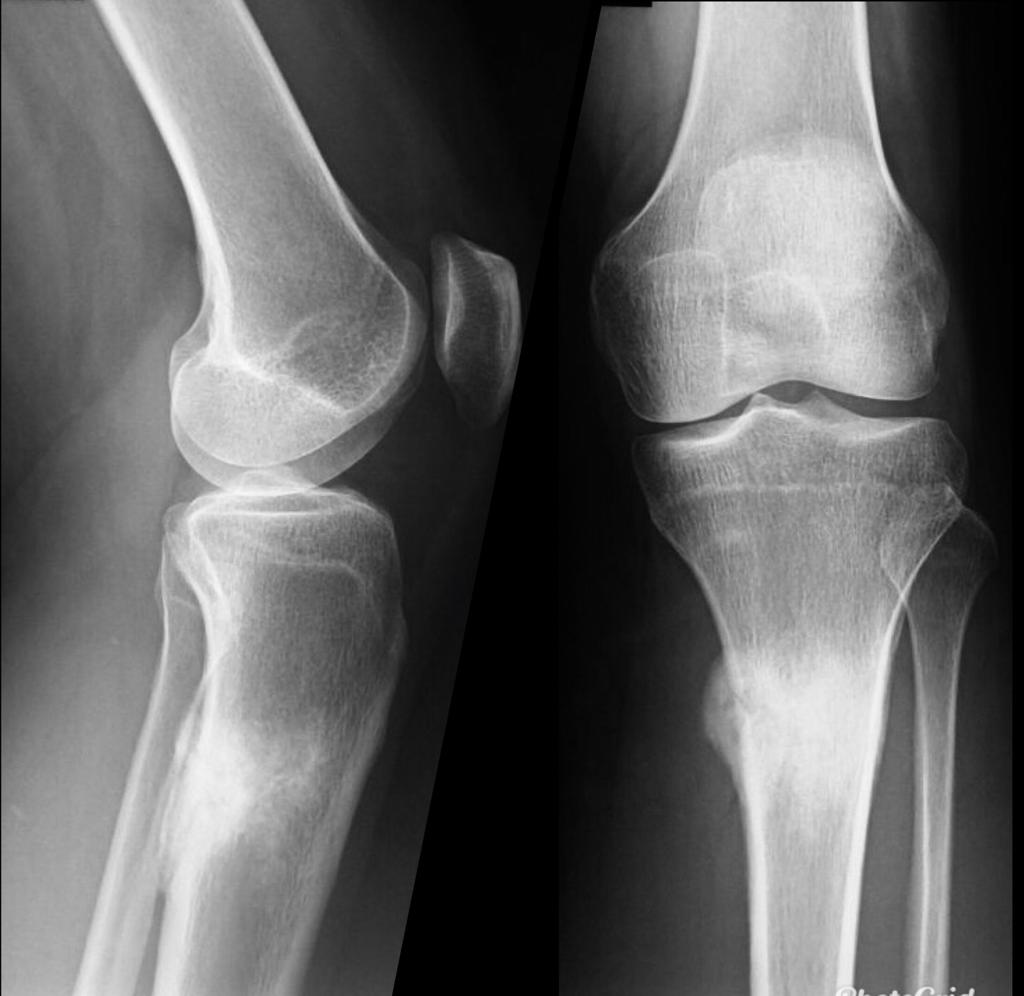

PATELLAR TENDON-LATERAL FEMORAL CONDYLE FRICTION SYNDROME

Patellar tendon-lateral femoral condyle friction syndrome, also known as Hoffa fat pad impingement syndrome, is a common cause of anterior knee pain in active individuals. It is thought to be due to patella maltracking or imbalance of the forces between medial and lateral vastus muscles causing impingement of the superolateral aspect of Hoffa fat pad between the inferior patella and the lateral femoral condyle.

Patients with Hoffa syndrome would present with acute or chronic sharp pain below the patella which is worsened by activities like walking, prolonged standing, wearing high heel shoes or any other activity that puts the knee into full extension. On examination, there may be swelling in the infrapatellar region, with point tenderness at the inferior pole of the patella.

The diagnosis is classically made with MRI and usually occult on radiography and CT. MRI findings include focal area of high T2 signal (edema) at the inferolateral aspect of the patellofemoral joint, within the superolateral portion of the infrapatellar fat pad. A cystic lesion can sometimes be found between the lateral femoral condyle and the lateral retinaculum. Associated findings include lateral patellar subluxation and patella alta (Insall-Salvati ratio greater than 1.2) which are found in around 90% of cases. Conservative treatment is usually successful, although full recovery may take time.